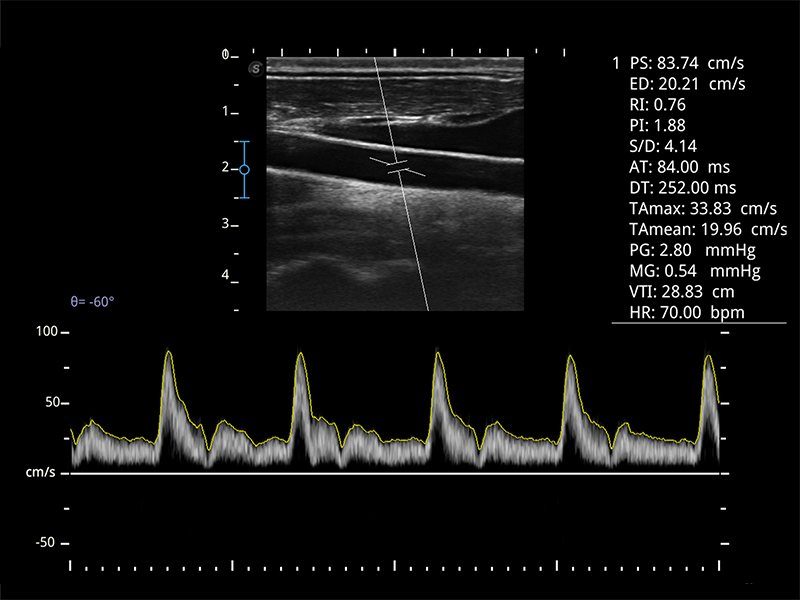

Doppler fali pulsacyjnej PW